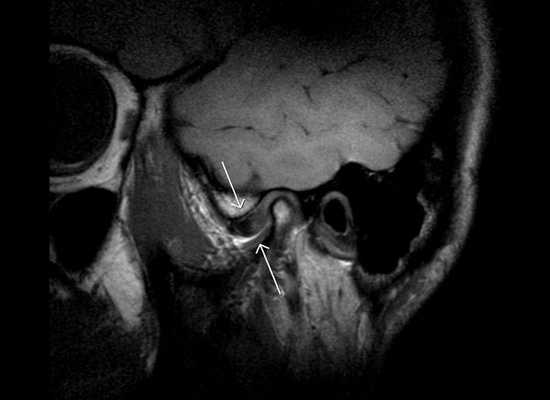

Изменения в височно-нижнечелюстном суставе

При нарушении функций или ограничении подвижности головок и суставных элементов развивается гипомобильность сустава, нарушается трофика его тканей. В зависимости от индивидуальных особенностей организма это может приводить к смещениям диска, появлению болей, хрустов и щелчков в суставе, а позже — к атрофии и деформации диска и суставных поверхностей [1] [2] .

Наблюдение за характером движений суставов, функциональные пробы и рентгенологические исследования (особенно ортопантомография) позволяют обнаружить осложнения со стороны височно-нижнечелюстного сустава и мышечной функции [4] [7] [8] [9] [12] . По показаниям проводятся КТ и МРТ данной области в положении открытого и закрытого рта.

Сбой работы височно-нижнечелюстного сустава может быть связан с его различными патологиями:

- хроническими заболеваниями сустава (артритом или артрозом);

- наследственными аномалиями (асимметрия ветвей нижней челюсти, аномалиями формы или размеров головок сустава);

- функциональными деформациями, возникшими, например, вследствие лечения кариеса и его осложнений.

При хроническом течении эти нарушения становятся причиной смещения челюстей, нарушения смыкания зубов и формирования перекрёстного прикуса [3] [4] [11] .